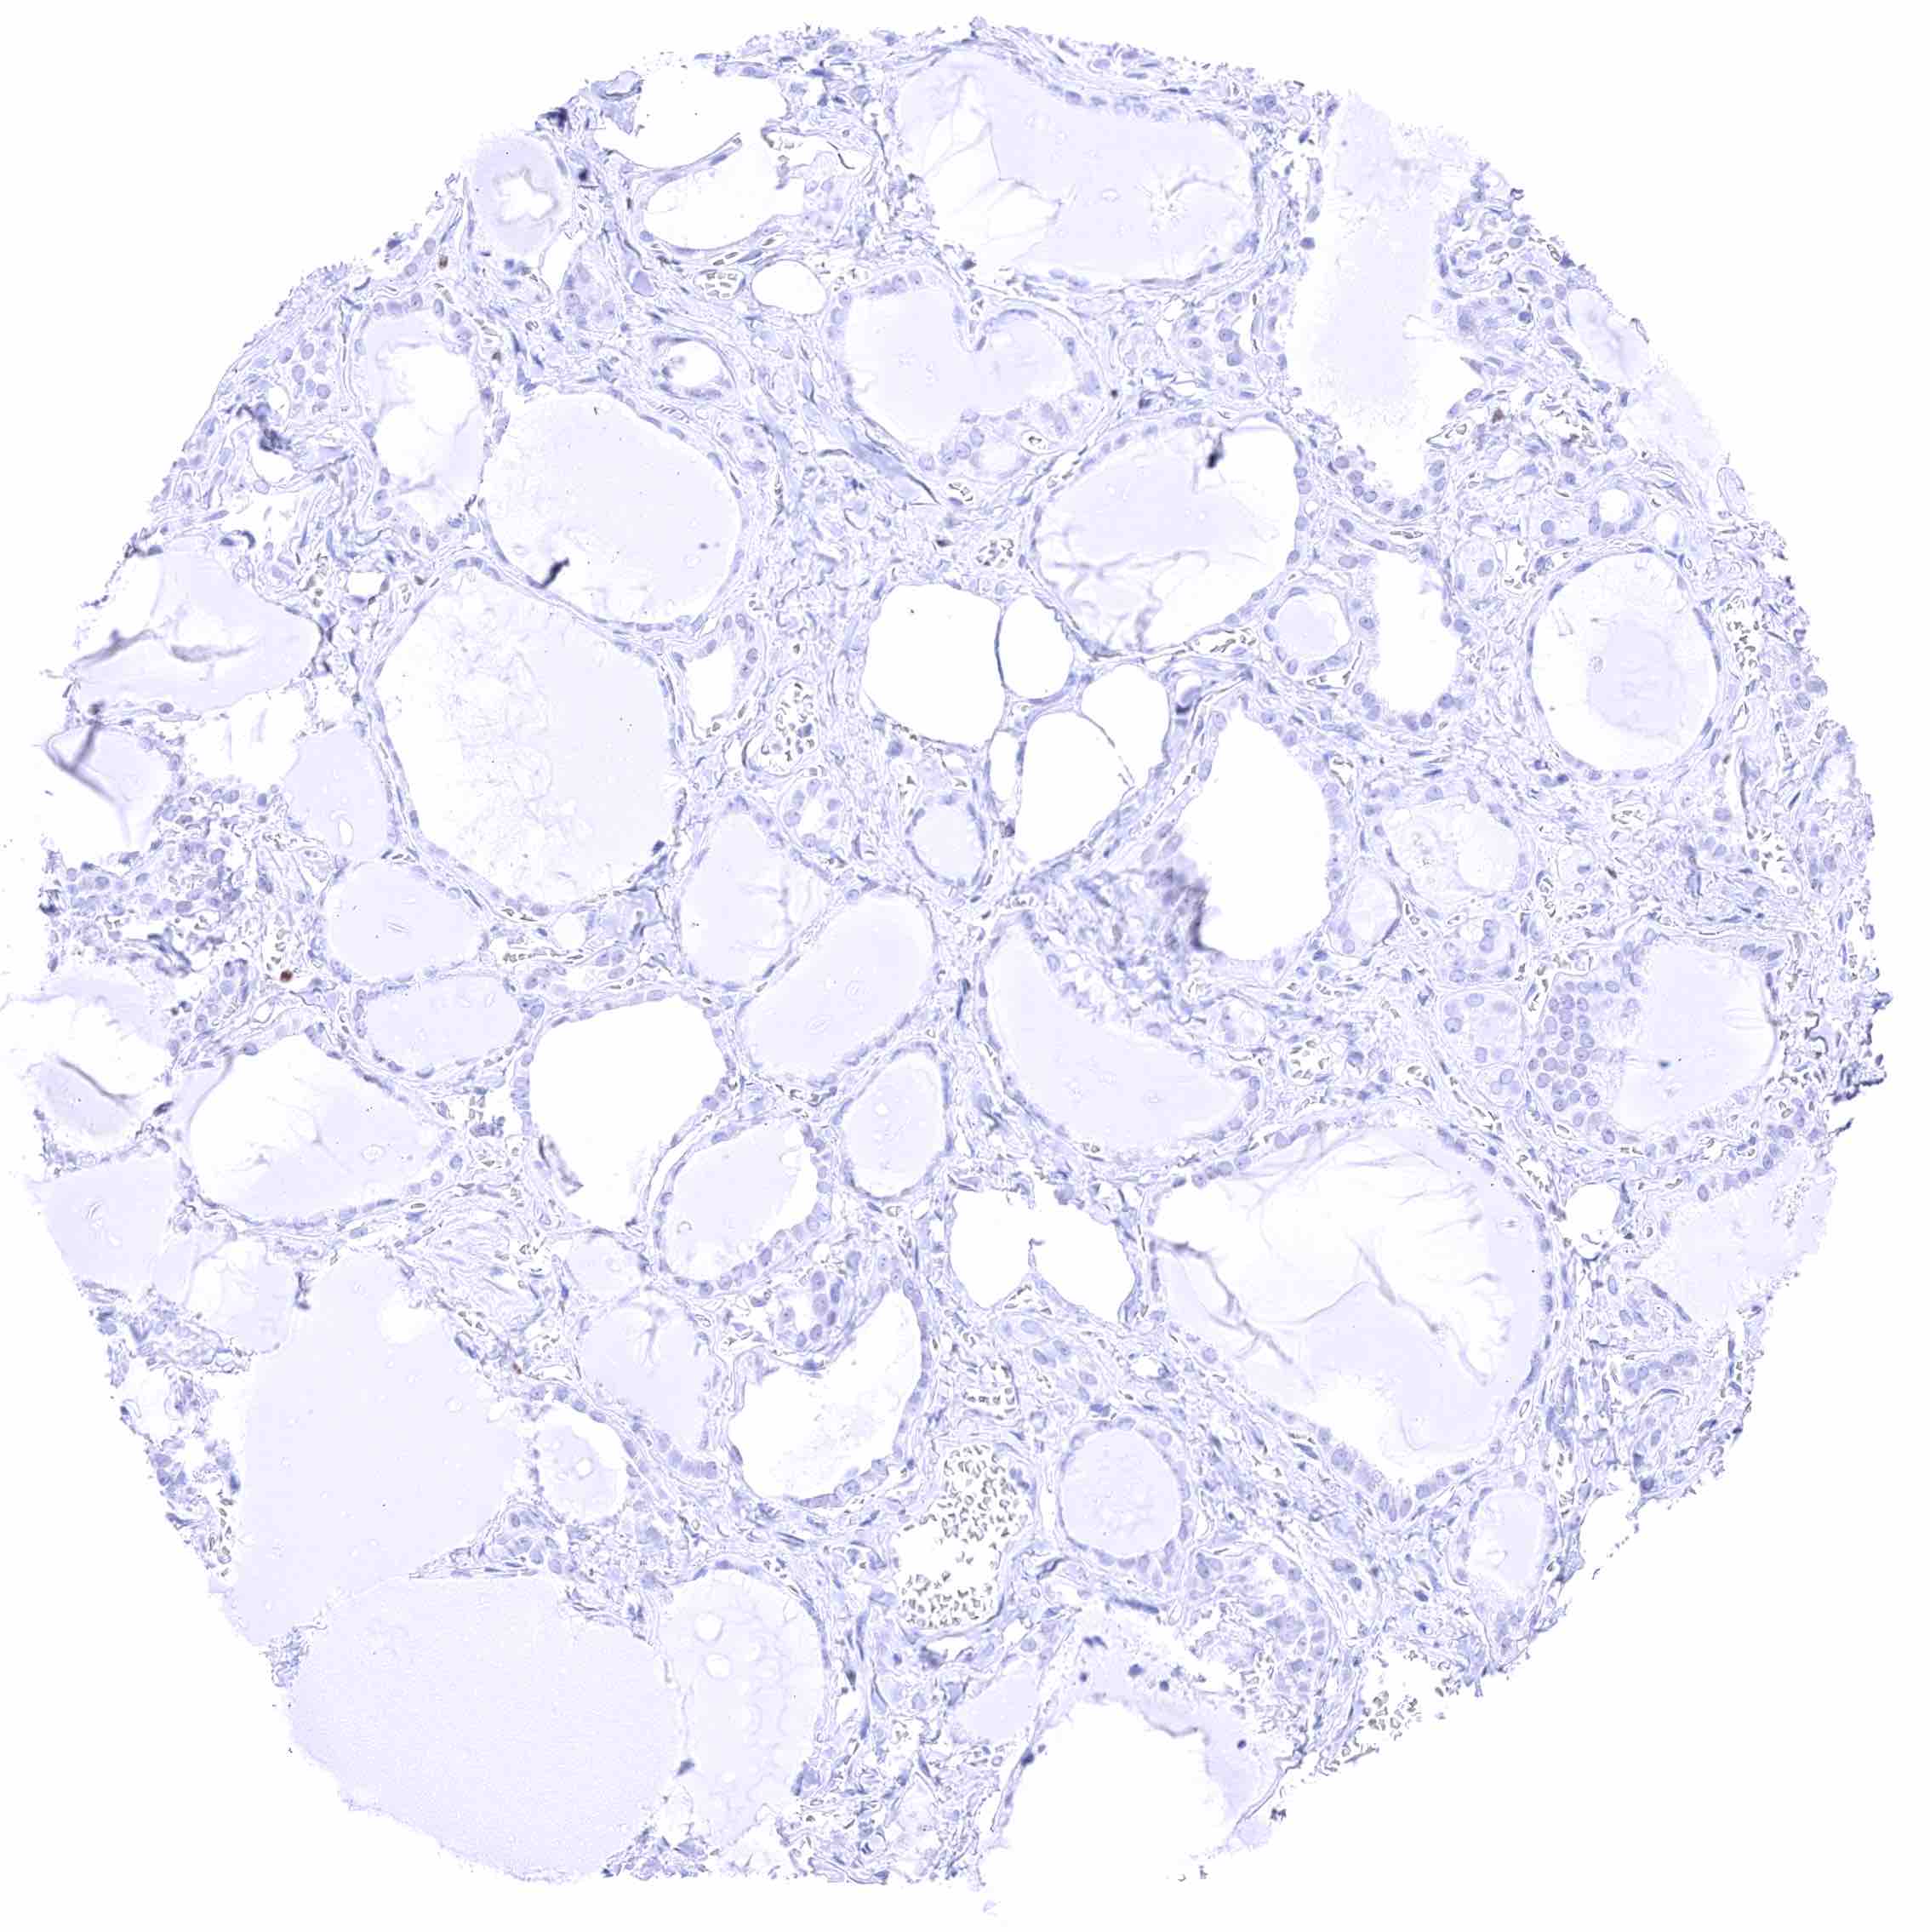

Ovary, follicular cyst

Ovary, stroma

Ovary, corpus luteum